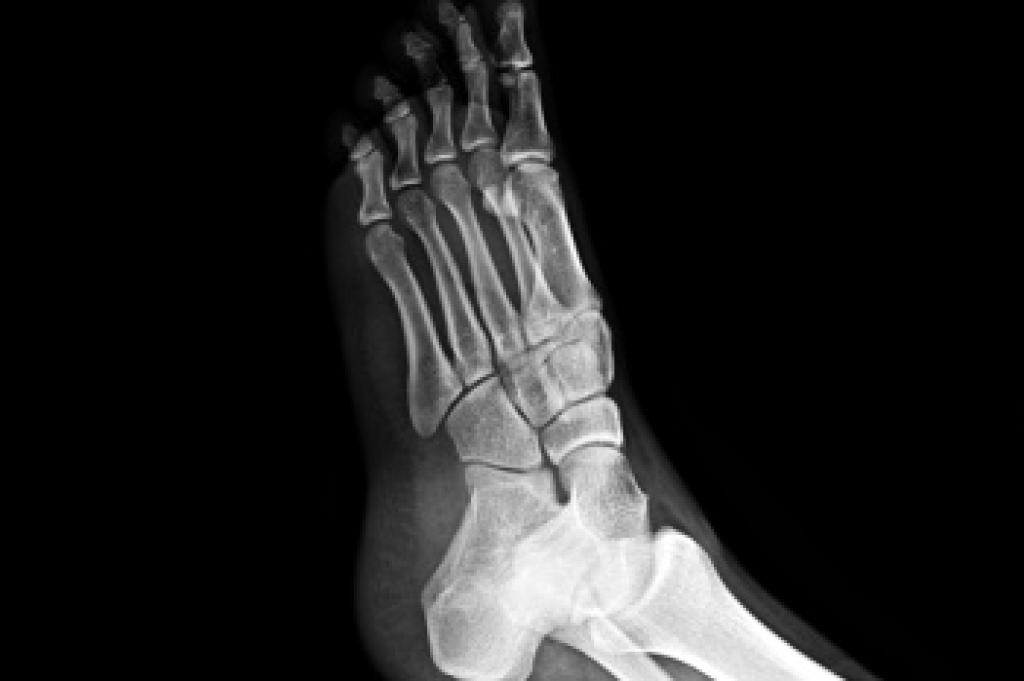

Metatarsal Bone Fractures

Metatarsal bone fractures occur when one of the long bones in the middle of the foot breaks, often from trauma, overuse, or a sudden twist. These fractures can be open, where the bone pierces the skin, or closed, where the skin remains intact. They may also be displaced, meaning the bone pieces are out of alignment, or nondisplaced, where the bone remains properly aligned. A podiatrist can assess the injury through examination and imaging, provide proper immobilization, and recommend treatment to promote healing and prevent long-term complications. Early diagnosis is vital to restoring foot function and mobility. If you have foot pain or feel you may have broken a bone, it is suggested that you promptly visit a podiatrist who can accurately diagnose and treat what is going on.

Broken Foot Causes, Symptoms, and Treatment

A broken foot is caused by one of the bones in the foot typically breaking when bended, crushed, or stretched beyond its natural capabilities. Usually the location of the fracture indicates how the break occurred, whether it was through an object, fall, or any other type of injury.